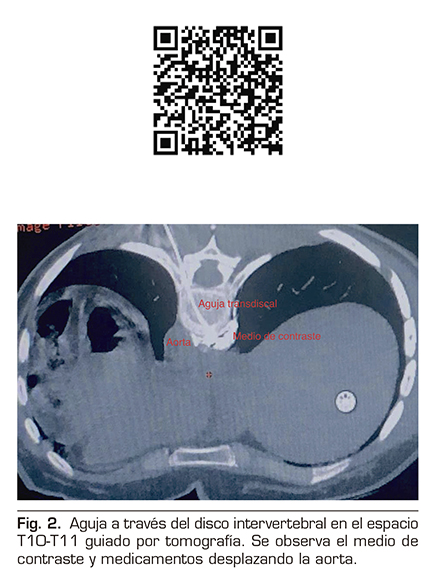

Figura 2